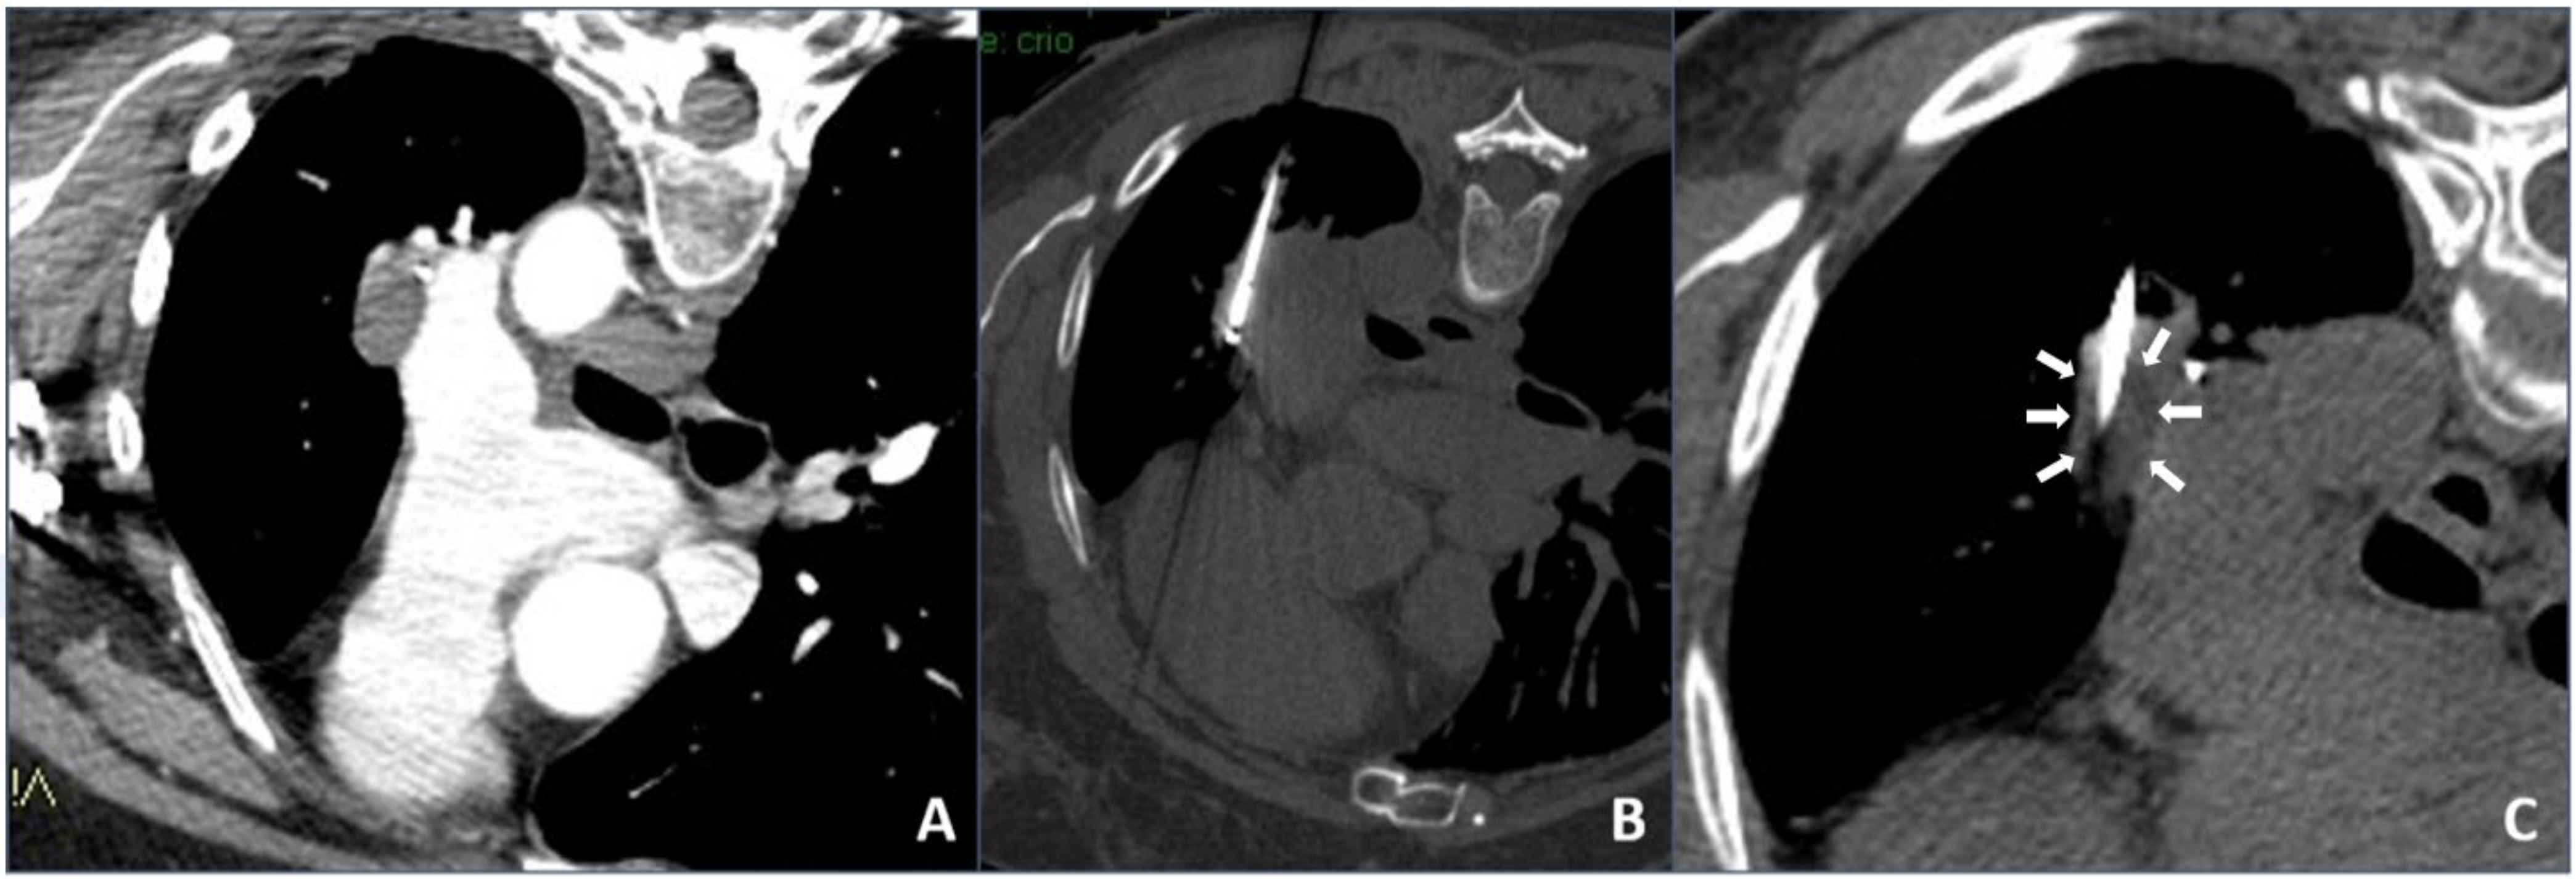

In our institution, it was decided to use cryoablation mainly in the case of unresectable complex chest lesions, usually contraindicated for heating ablation, after discussion in our internal multidisciplinary tumor board: They were tumors located close (<1 cm) to large vessels/hilum/hearth and mediastinal structures in which heat sink effect might lead to thermal ablation failure or to a vessel injury (an example is shown in Figure 2).

Figure 2.

Cryoablation procedure: (A) contrast-enhanced axial CT scan showing a left hilum neoplastic lesion adjacent to the left pulmonary artery; (B) intra-procedural unenhanced axial CT scan with maximum intensity projection (MIP) reconstruction showing the cryoablation needle inside the lesion; (C) intra-procedural unenhanced axial CT scan with MIP reconstruction showing direct visualization of the hypodense core necrotic volume.